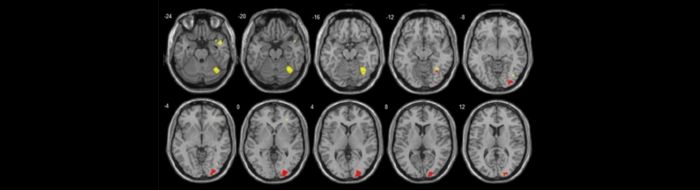

In grapheme-colour synaesthesia (GCS), people see certain letters (known as inducers) as having specific colours (known as concurrents). These additional perceptual experiences provide a unique window onto the neural mechanisms of consciousness, which we are exploring in a large-scale fMRI study comparing synaesthetes and controls. A key question is whether synaesthetic colour experiences activate colour-specific brain regions in the cortex (e.g., V4). The existing literature is rather mixed on this point, so we are examining how individual differences in how synaesthetes experience their additional colours may account for differences in their brain responses. We are also interested in seeing whether synaesthetes process real colours differently from non-synaesthetes.

Gould, C.G., Garfinkel, S., Bor, D., Ward, J., and Seth, A.K. (2013). BOLD activation in colour-selective areas is modulated by subjective experience in grapheme-colour synaesthesia. Association for the Scientific Study of Consciousness, 17th Annual Meeting, San Diego, CA.